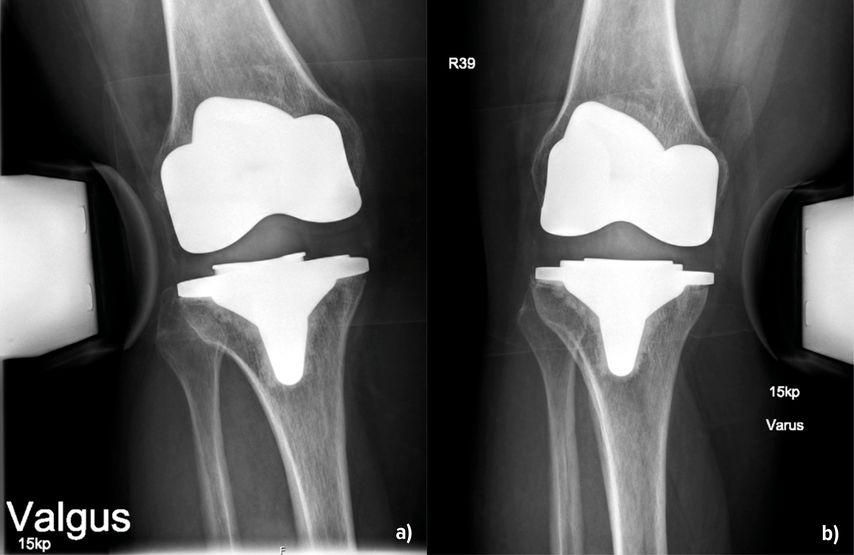

Abb. 2: 53-jährige Patientin 14 Monate nach KTEP-Implantation mit klinisch und radiologisch (a und b) nachweisbarer Instabilität – medial stärker als lateral

Die Instabilität von Knietotalendoprothesen beeinflusst die Zufriedenheit der Patient:innen und führt häufig zu Revisionseingriffen. In einer grossen retrospektiven Studie mit Erfassung von fast 40000 Patient:innen aus den Jahren 1996–2021 konnten Ergin et al. (2025) Risikofaktoren, welche mit einer Instabilität nach Endoprothetik einhergehen, darstellen. Dazu gehörten ein jüngeres Alter, das weibliche Geschlecht, ein Schlaganfall, tiefe Beinvenenthrombosen, Nickelallergie, Osteoporose und – überraschend – die Sklerodermie. Die Adipositas stellt demnach kein erhöhtes Risiko dar. Über die Details der Ursachen berichtet die Arbeit allerdings nicht, sondern beschreibt diese als multifaktoriell. Jedoch können die Autoren aus der eigenen klinischen Praxis berichten, dass durchaus Unterschiede in Bezug auf das Inlay bestehen. Entweder war dieses primär zu flach oder es ist zu einer Lockerung der Bänder im Verlauf gekommen. Auch der Verschleiss des Inlays über die Zeit spielt erfahrungsgemäss eine Rolle (Abb. 1). Bei der Differenzierung, welches Ausmass einer Varus- oder Valguslaxizität zu einem annehmbaren oder schlechten klinischen Ergebnis führt, fanden Mitsu-Uchi et al. (2025), dass eine mittlere Instabilität von 3–6mm im medialen Kompartiment für ein besseres postoperatives Ergebnis von Bedeutung sei. Eine straffe Implantation mit einer Instabilität von <3mm sowie Instabilitäten von >6mm führten demnach zu niedrigeren Zufriedenheitswerten bzw. Knee-Scores. Somit soll eine mittlere mediale Laxizität für ein besseres postoperatives Ergebnis sorgen, was bereits bei der Implantation Beachtung finden kann. Neben dem klinischen Nachweis ist die gehaltene Röntgenaufnahme geeignet, um den Befund zu verifizieren und zu dokumentieren (Abb.2). Bezüglich der Ursachen für Fehlschläge primärer Knietotalendoprothesen finden sich die Instabilitäten mit einer Häufigkeit von 7% bzw. 4,55% an 3. bzw. 4. Stelle. Vorwiegende Gründe für Revisionen sind hingegen periprothetische Infektionen (22,3% bzw. 47,73%), die aseptische Lockerung (20,5% bzw. 35,23%) und Bewegungseinschränkungen (5,68%) (Datta et al. 2025, Mozella et al. 2024). In einer Arbeit von Poilvache et al. (2025) wurde das Übergewicht als Risikofaktor für Komplikationen nach K-TEP untersucht. Die Hauptursachen für die initiale Revision waren die aseptische Lockerung mit 37%, die Instabilität (29%) und der Abrieb oder Osteolysen (13%). Die Arbeit erbrachte ganz klar, dass ein BMI >40kg/m2 tendenziell mit einer Reoperation korrelierte. Allerdings nicht wegen Instabilität, sondern wegen periprothetischer Infektionen, und das auch nicht signifikant. Der BMI als Ursache einer Instabilität nach Revision wurde hier ausgeschlossen. Brown et al. (2025) beschrieben ein erhöhtes Risiko mit Hinblick auf eine Revision als Folge einer Instabilität oder einer Lockerung bei Fällen, in denen die Femurkomponente grösser als die Tibiakomponente war. Die Autoren empfahlen, primär die Wahl der Prothesengrössen zu beachten, um Instabilitäten vorzubeugen. Auf die Infektionsraten und den anterioren Knieschmerz fand sich in dieser Kohorte kein Einfluss.